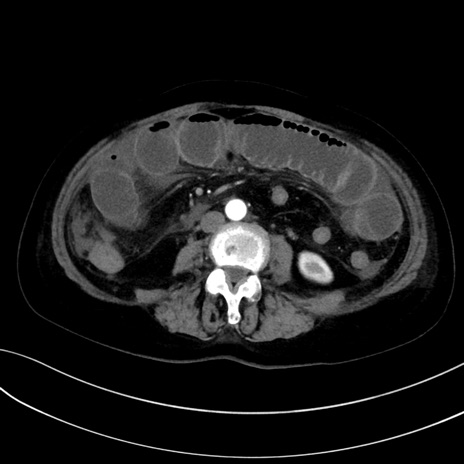

症例13 CT(横断像)1日半後